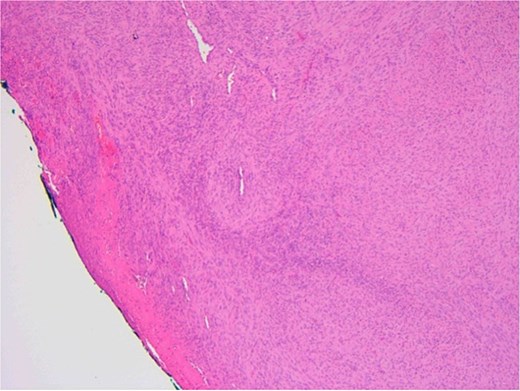

The patient underwent a biopsy of the lesion. Histopathological analysis revealed spindle cell proliferation arranged in a fascicular growth pattern, dilated hemangiopericytoma-like vessels, and a central myeloid nodule. Immunohistochemical staining was positive for smooth muscle actin (SMA), with no evidence of cellular atypia (Figs 5–7).

Ulcerated area with underlying bland spindle cell proliferation showing fascicular growth impression of cellularity involving vascular wall – haemangiopericytoma-like architecture (central).